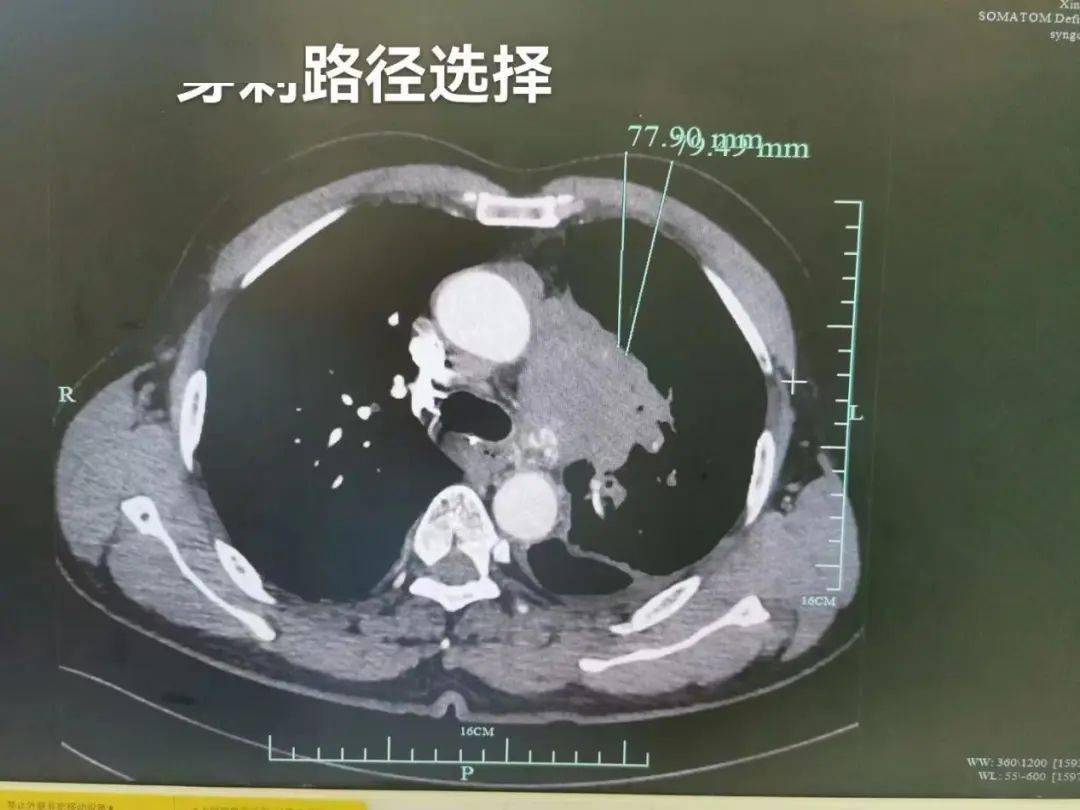

1.手术穿刺路径的选择,穿刺路径要尽量避开肺大泡,避开叶间裂及肺气肿的严重区域。

6.纵隔肿块的活检路径尽量选择经皮直接入纵隔的路径,尽量不要选择经皮、肺部再入纵隔的路径,以免两次穿透不同部位的完整胸膜而徒增气胸风险。